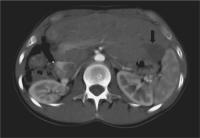

Abbildung 1: Axiale CT-Schicht ohne KM. CT-gezielte Plazierung einer Schirmelektrode im expandierten Zustand (Pfeil).